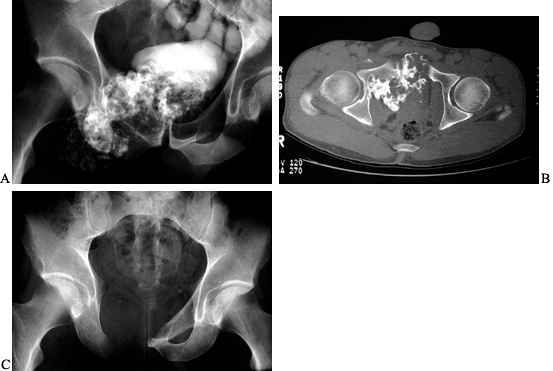

Figure 126.10. A: AP radiograph of the knee and proximal tibia from a 15-year-old boy. An osteosarcoma involves the upper tibia. B: Lateral radiograph of tibial osteosarcoma. C:

AP radiograph after resection of the upper tibia (intra-articular) and allograft arthrodesis. Note the intramedullary rod and screws for fixation. D: Lateral radiograph showing fusion of the knee. |